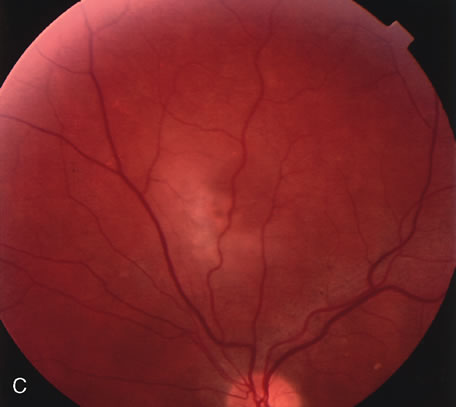

Fig. 29. 14-year-old adolescent girl with sudden loss of vision in the left eye to 20/400. A. Clinical photograph of the posterior pole demonstrates a neurosensory macular detachment simulating central serous chorioretinopathy. B. Composite fundus photograph of the same eye demonstrates the presence of a localized area of retinal capillary telangiectasia in the temporal periphery. The intraretinal yellowish material is consistent with dehemoglobinized blood. There are also intraretinal exudates scattered throughout the fundus. C. Composite fluorescein angiogram of the same eye reveals diffuse retinal capillary telangiectasia and intraretinal leakage. The dilated retinal telangiectatic vessels are actively leaking and are responsible for the macular neurosensory detachment. This patient was diagnosed with Coats' disease. D. Scatter laser photocoagulation of the telangiectatic vessels was carried out.